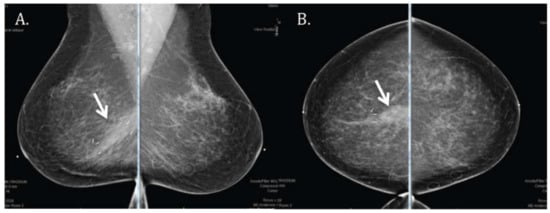

3.2. Radiologic Correlate

The most common finding on the six-month follow-up mammogram (Figure 4) was the presence of a post-surgical scar with tumor bed clips. Examples of other possible findings, such as skin thickening, are shown in Figure 5. An analysis of all mammographic outcomes at six months is shown in Figure 6. Forty percent of the patients had skin thickening at six months. However, this was generally mild, ranging from 0 mm to only 5.5 mm. Retraction/asymmetry was seen in 26% (n, 11) of the patients, and graded as mild in 9/11. The presence of a seroma/hematoma was reported in 14% of the cases, while fat necrosis was a rare finding present in only one patient at six months.

Figure 4. Mammographic evaluation showing (A) medio-lateral oblique and (B) cranio-caudal views of a common radiologic finding after proton APBI to the right breast at the six-month follow-up visit: post-surgical scar (arrow) and tumor bed clips.